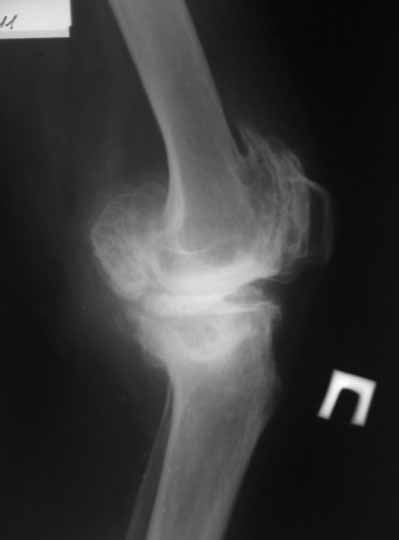

Пациентка 72 лет.Не обследовалась и не лечилась.

Работала поварихой до последнего времени. обратилась за медпомощью впервые. ходит без

дополнительной опоры. Основные жалобы на ограничение движений и боли в правом коленном

суставе. Финансовые возможности ограничены. Чем можно помочь? Артродез? Протезирование?